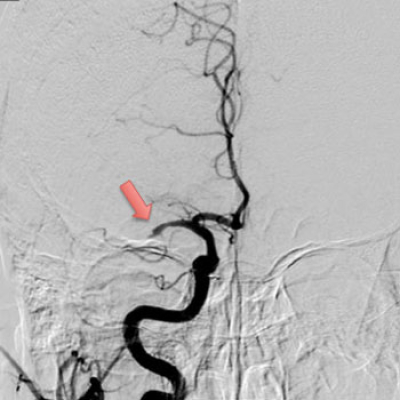

Interview with Jeffrey L Saver, M.D., author of Time to Treatment With Endovascular Thrombectomy and Outcomes From Ischemic Stroke: A Meta-analysis